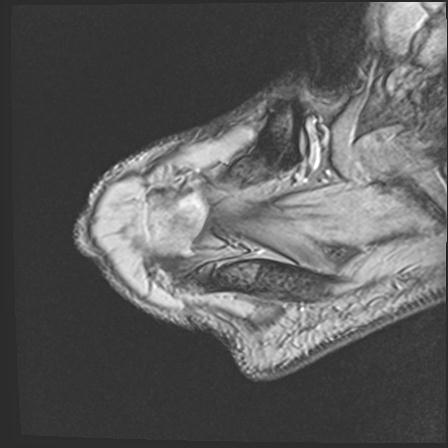

60058 3/9 11/4 右肩 2R+MRI 73歳男性 肩腱板損傷